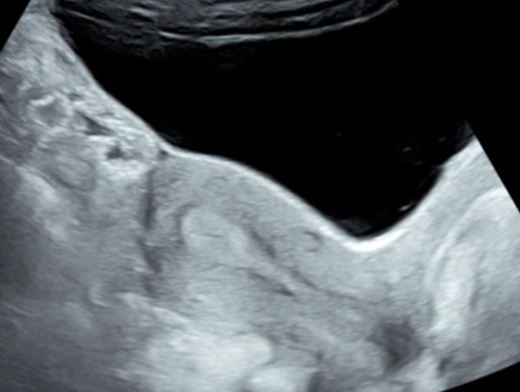

Mme G. est finalement césarisée sous anesthésie générale sans complication. Lors de l’hystérotomie, le liquide amniotique est sanglant avec de nombreux caillots. Les pertes sanguines sont estimées à 1 500 mL. L’équipe d’anesthésie a administré en peropératoire un culot de globules rouges et un plasma frais congelé (PFC), ainsi que de l’acide tranexamique. L’utérus est tonique en fin d’intervention. Au cours de la surveillance en salle de surveillance post-interventionnelle (SSPI), à quatre heures postopératoires, Mme G. a une barre épigastrique résistante aux antalgiques de palier 3. Les constantes sont les suivantes : pression artérielle = 190/110 mmHg ; fréquence cardiaque = 120 bpm ; saturation en oxygène = 99 % en air ambiant. Compte tenu de la tachycardie, vous réalisez une échographie transabdominale dont les images sont les suivantes. Figure 2a (Rodolphe Matias de Sousa, La Revue du Praticien)Figure 2b (Rodolphe Matias de Sousa, La Revue du Praticien)Figure 2c (Rodolphe Matias de Sousa, La Revue du Praticien) Vous décidez d’avancer le prochain bilan biologique et récupérez les résultats suivants : hémoglobine = 8,7 g/dL ; plaquettes = 40 G/L ; TP = 65 % ; TCA = 1,02 ; fibrinogène = 2 g/L ; haptoglobine indosable ; ASAT = 260 UI/L ; ALAT = 240 UI/L.

Concernant l’hématome sous-capsulaire du foie : Tableau 3 (Rodolphe Matias de Sousa, La Revue du Praticien) Concernant l’échographie transabdominale à la recherche d’un hémopéritoine :on regarde deux espaces, le cul-de-sac de Douglas entre l’utérus et le rectum, et l’espace de Morrison entre le foie et le rein. Figure 3a (Rodolphe Matias de Sousa, La Revue du Praticien)Figure 3b (Rodolphe Matias de Sousa, La Revue du Praticien)Figure 3c (Rodolphe Matias de Sousa, La Revue du Praticien) Pour rappel, concernant l’échographie en gynécologie : Figure 4a (Rodolphe Matias de Sousa, La Revue du Praticien)Figure 4b (Rodolphe Matias de Sousa, La Revue du Praticien)Figure 4c (Rodolphe Matias de Sousa, La Revue du Praticien)Figure 4d (Rodolphe Matias de Sousa, La Revue du Praticien)Figure 4e (Rodolphe Matias de Sousa, La Revue du Praticien)Figure 4f (Rodolphe Matias de Sousa, La Revue du Praticien)Figure 4g (Rodolphe Matias de Sousa, La Revue du Praticien)Figure 4h (Rodolphe Matias de Sousa, La Revue du Praticien)Figure 4i (Rodolphe Matias de Sousa, La Revue du Praticien)